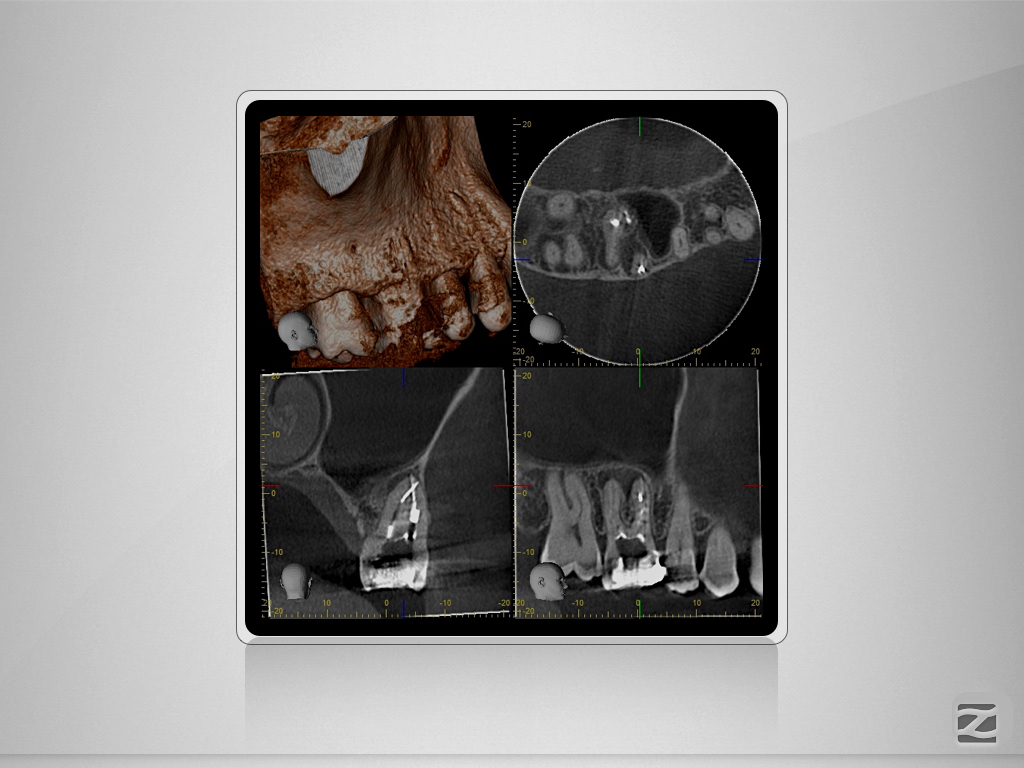

16D.002

Multiple Fragmente